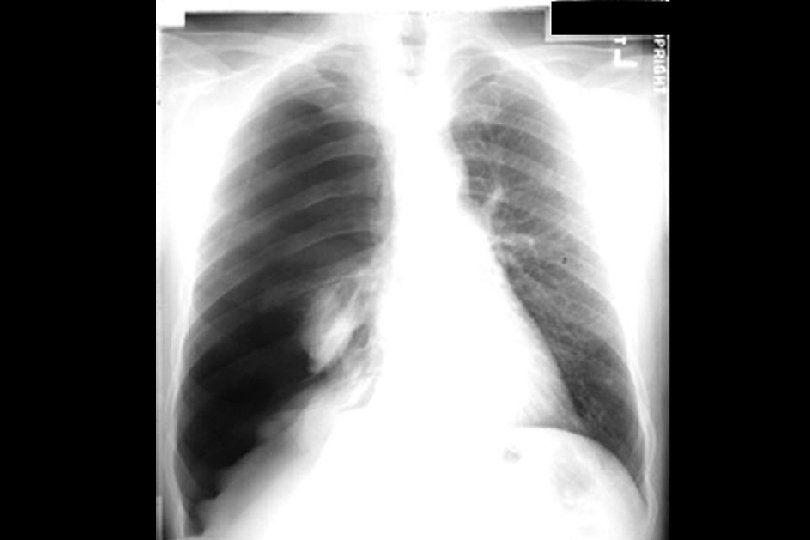

Pleural effusion LUL cavity Tuberculosis